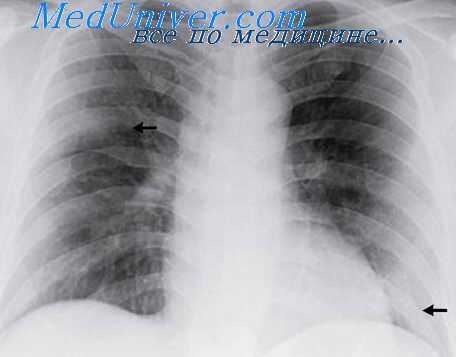

Визуализация

Рентгенологическое исследование имеет меньшую диагностическую ценность по сравнению с компьютерной томографией (КТ и КТВР КТВР - компьютерная томография высокого разрешения

Тяжелый ОРДС предполагает затемнение минимум 3-4 полей.

Характерная рентгенологическая находка - возникновение картины “матового стекла” и диффузных мультифокальных инфильтратов довольно высокой плотности с хорошо очерченными воздушными бронхограммами, то есть развитие обширного поражения паренхимы легких.

Часто может визуализироваться небольшой плевральный выпот.

Определенные трудности возникают при дифференциации рентгенографической картинй ОРДС с кардиогенным отеком легких. В пользу ОРДС свидетельствуют:

- более периферическое расположение инфильтративных теней;

- нормальные размеры сердечной тени;

- отсутствие или небольшое количество линий Керли Линии Керли - горизонтальные линейные тени на рентгенограмме нижних отделов легких, наблюдаемые при уплотнении (отеке) междольковых перегородок, например у больных с легочной гипертензией

типа В (короткие, параллельные, располагающиеся на периферии легких).